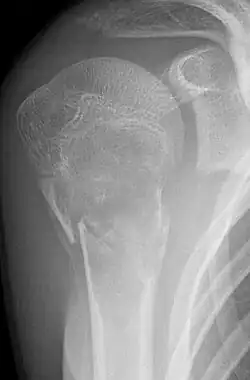

Eine Knochenzyste ist eine gutartige tumorähnliche Knochenläsion, welche einen flüssigkeitsgefüllten und z. T. zellgefüllten Hohlraum im Knochen darstellt. Radiologisch erkennt man hier im Röntgenbild eine ein- oder mehrkammerige Aufhellung. Die Zysten im jugendlichen Knochen werden meist als Zufallsbefund beim Röntgen nach Unfallverletzung oder als Ursache von sogenannten pathologischen Frakturen (Frakturen bei verringerter Knochenfestigkeit) entdeckt.

- Einfache (juvenile) Knochenzyste: Gutartige, primär einkammerige, flüssigkeitsgefüllte Höhle, meist im metaphysären Markraum. Wird meist erst durch Spontanfraktur auffällig. Klassisches Röntgenzeichen ist das Fallen-Fragment-Sign.